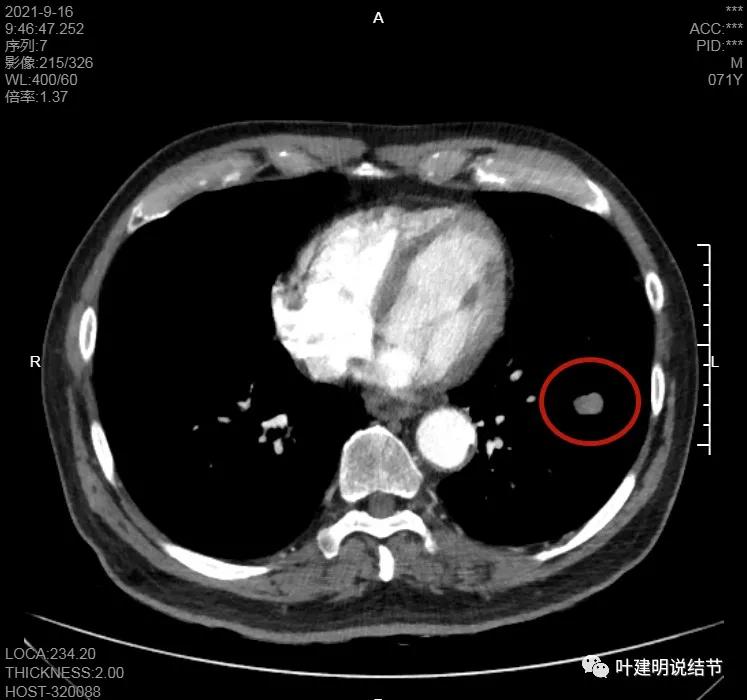

纵隔窗上也是很光滑的,据CT报告其强化也不明显:

左下病灶在增强CT中强化不明显,但有肺门区肿大淋巴结,而且近3厘米大。同事叫我看片子的时候,本来只先看左下病灶处,以为是良性结节。但翻到肺门区,发现有如此大的肿大淋巴结,那这个原发灶则肯定是恶性的了!我们先来看纵隔窗的淋巴结情况:

左肺门区淋巴结肿大

肺门区淋巴结挤压附近肺血管,但似乎示见肿瘤侵犯破坏血管壁